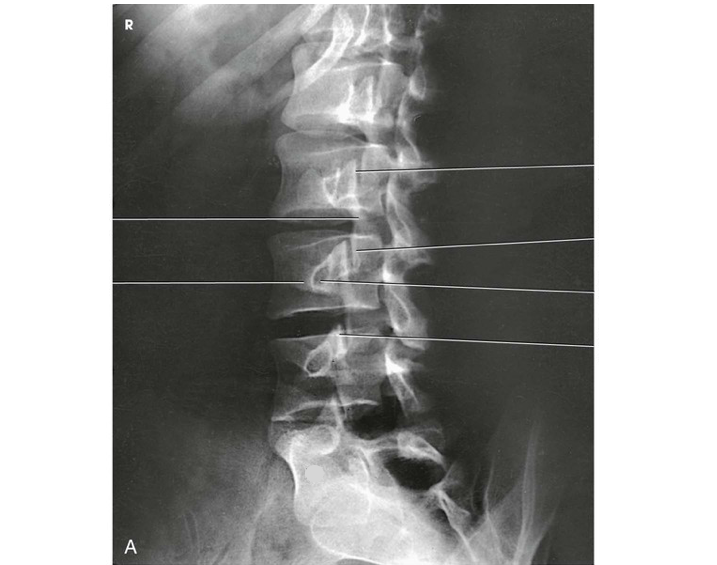

Question

Label the image

bf02d4b3-b413-4b88-83ee-ab11b96c3395 (image/png)

Answer

L5

S1

intervertebral disk space

sacrum

sacroiliac joint

ilium